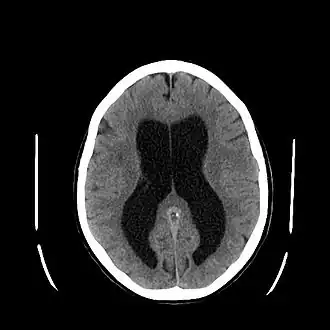

L’hydrocéphalie (du grec ancien ὕδωρ / húdôr (« eau ») et κεφαλή / kephalế (« tête »)) est une anomalie neurologique sévère, définie par l'augmentation du volume des espaces contenant le liquide cérébrospinal (LCS) : ventricules cérébraux et espace subarachnoïdien. Cette dilatation peut être due à une hypersécrétion de LCS, un défaut de résorption, ou une obstruction mécanique des voies de circulation. Dans les familles issues de mariages entre apparentés, l'enfant consanguin a 13 fois plus de risques de développer une hydrocéphalie[1].

- Le scanner cérébral (sans injection d'iode) retrouve une dilatation quadriventriculaire sans élargissement des sillons corticaux sur l'ensemble de la convexité corticale et un arrondissement des angles latéraux des ventricules (ce qui permet de différencier hydrocéphalie et atrophie cérébrale).

- L'IRM cranioencéphalique est devenu l'examen de référence. Il permet de mettre en évidence la dilatation des ventricules et des anomalies périventriculaires